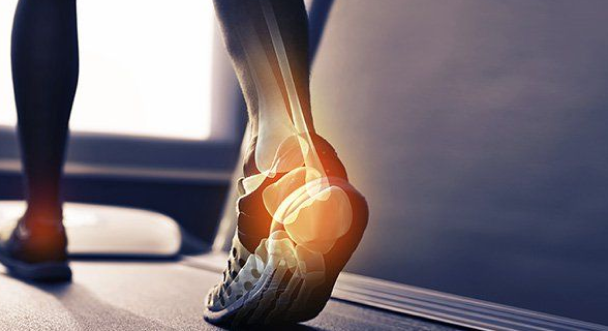

خار پاشنه یک رسوب کلسیم است که باعث بیرون زدگی استخوانی در زیر استخوان پاشنه می شود. در یک اشعه ایکس ، خار پاشنه می تواند تا نیم اینچ به جلو گسترش یابد. بدون وجود شواهد اشعه ایکس قابل تشخیص است، این بیماری گاهی اوقات به عنوان “سندرم خار پاشنه” شناخته می شود. اگرچه خار پاشنه اغلب بدون درد است، اما می تواند باعث درد پاشنه شود. آنها غالباً با فاسئیت کف پا یا التهاب دردناک باند رشته ای بافت همبند (فاسیای کف پا) همراه هستند. این ناحیه در امتداد پایین پا قرار گرفته و استخوان پاشنه را به انگشتان پا متصل می کند.

خار پاشنه هنگامی ایجاد می شود که رسوبات کلسیم در زیر استخوان پاشنه جمع می شود، این فرآیند معمولاً در طی چند ماه اتفاق می افتد. خار پاشنه اغلب به دلیل کشیدگی عضلات پا و رباط ها، کشش فاشیای کف پا و پارگی مکرر غشایی است که استخوان پاشنه را می پوشاند. خار پاشنه مخصوصاً در بین ورزشکارانی دیده می شود که فعالیت آنها شامل مقدار زیادی دویدن و پریدن است.

اغلبافراد مبتلا هیچ علامتی ندارد. اما غالبا خار پاشنه همراه با درد خفیف و یا مزمن همراه می باشد – به خصوص هنگام راه رفتن ، آهسته دویدن یا دویدن – در صورت ایجاد التهاب در نقطه تشکیل خار. جالب است بدانید به طور کلی ، علت درد مربوط به وجود خود خار پاشنه نیست بلکه به آسیب ایجاد شده بافت نرم مرتبط با آن مربوط است. بسیاری از افراد درد خار پاشنه و ورم کف پا را مانند چاقو یا سوزن چسبیده به پایین پاهایشان هنگام اولین ایستادن صبح توصیف می کنند. آنها غالباً شکایت دارند که پس از ایستادن و بعد از مدت طولانی نشستن ، درد شدید برمی گردد.